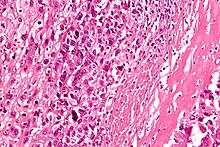

| Intermediate-magnification micrograph of an osteosarcoma (center and right of image) adjacent to non-malignant bone (left-bottom of image): The top-right of the image has poorly differentiated tumor. Osteoid with a high density of malignant cells is seen between the non-malignant bone and poorly differentiated tumor (H&E stain). | |

Microscopically: The characteristic feature of osteosarcoma is presence of osteoid (bone formation) within the tumor. Tumor cells are very pleomorphic (anaplastic), some are giant, numerous atypical mitoses. These cells produce osteoid describing irregular trabeculae (amorphous, eosinophilic/pink) with or without central calcification (hematoxylinophilic/blue, granular)—tumor bone. Tumor cells are included in the osteoid matrix. Depending on the features of the tumor cells present (whether they resemble bone cells, cartilage cells, or fibroblast cells), the tumor can be subclassified. Osteosarcomas may exhibit multinucleated osteoclast-like giant cells.[18]